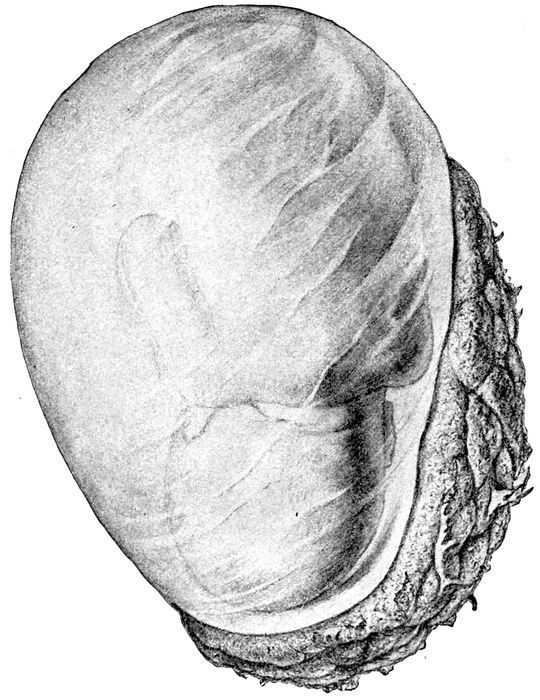

Fig. 19.—The egg at term with uterus removed and child showing through the membranes. (Edgar.)

Fig. 21.—Fœtal skulls showing sutures. Note the differences between the anterior and posterior fontanelles. (Eden.)